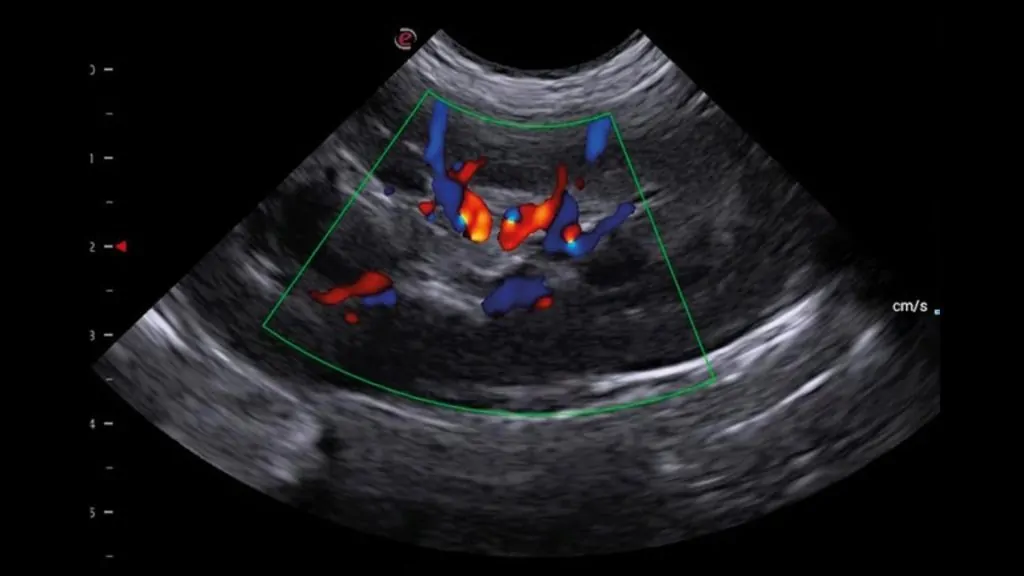

1) Doğumsal Kalp Hastalıkları

• Patent Ductus Arteriosus (PDA)

• Ventriküler Septal Defekt (VSD)

• Atriyal Septal Defekt (ASD) ve diğer doğumsal anomalilerin saptanması ve hemodinamik etkilerinin değerlendirilmesi